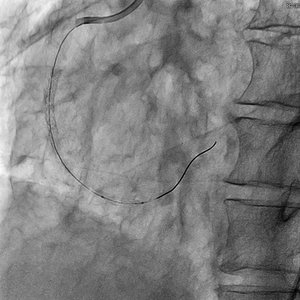

撮影よりも低線量の透視において、更に半分のフレームレートでも十分な視認性を確保している。